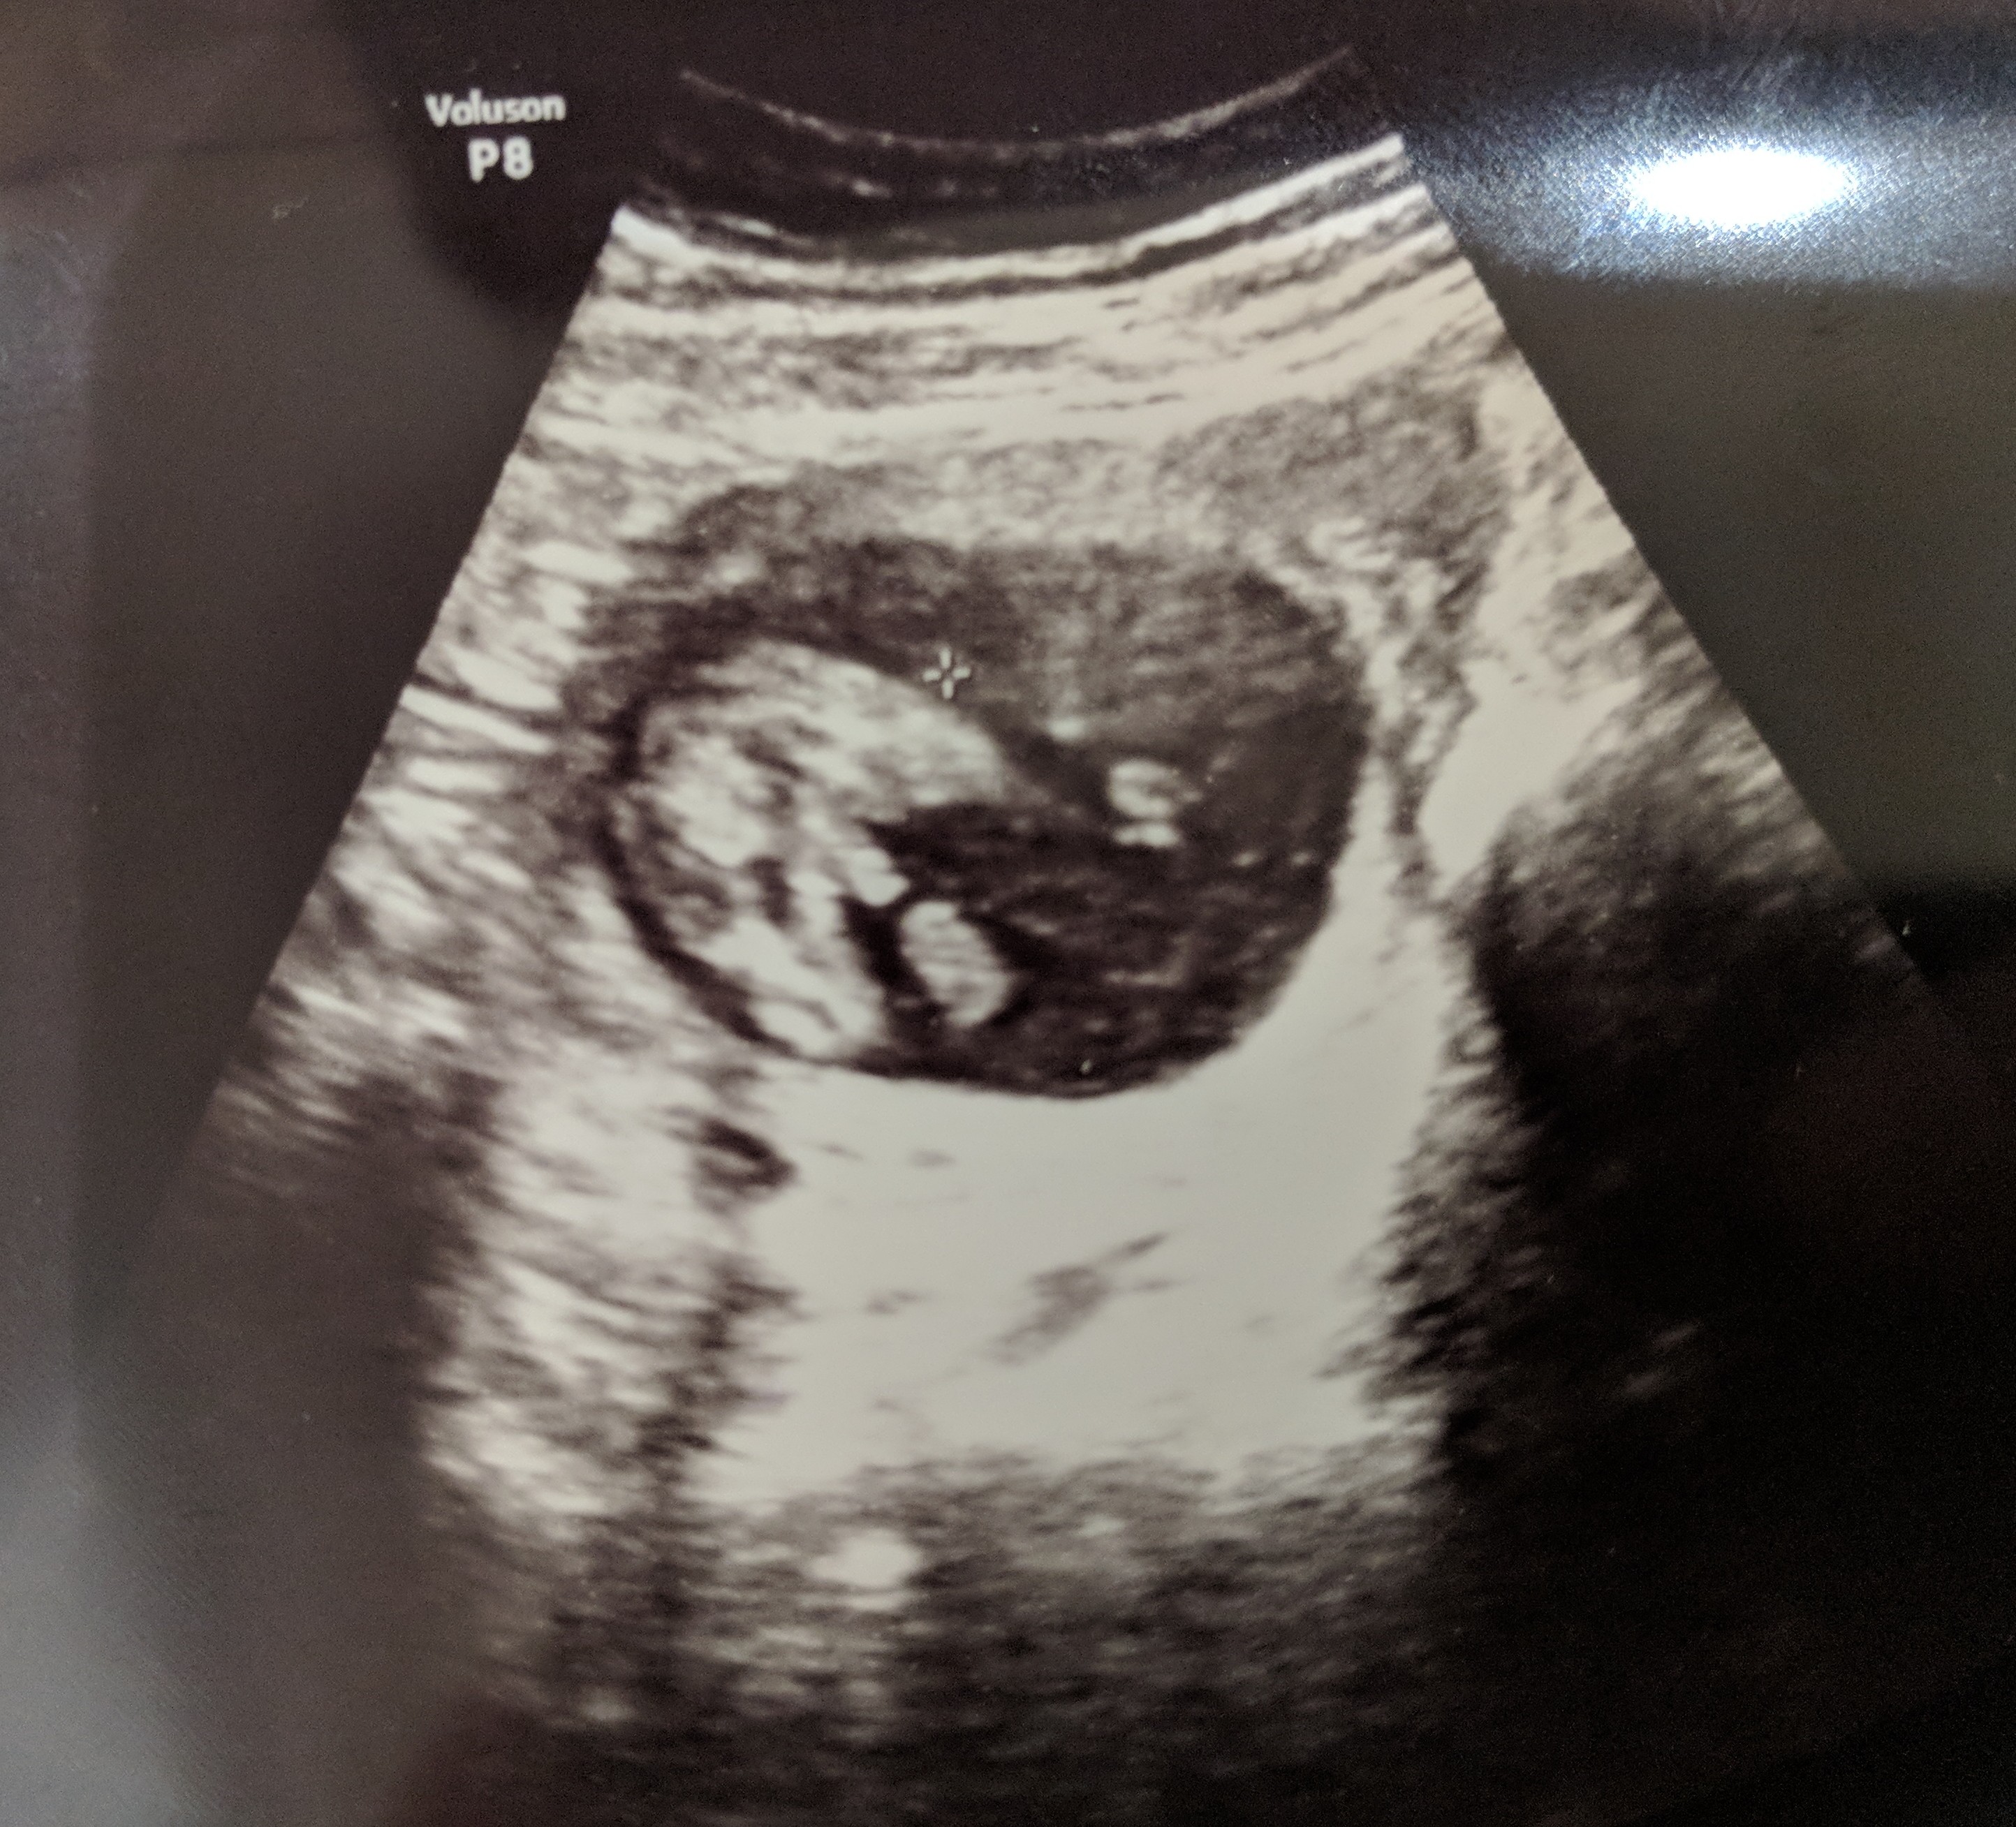

Attachment 40073 16 weeks. What do you think?

thats a boy :)

Boy!